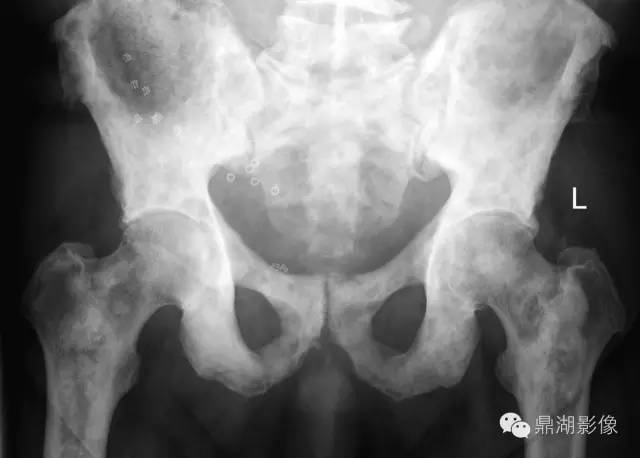

70岁,男,前列腺癌患者

X线片表现:成骨性转移表现为在骨外型没有改变的骨背景上出现圆形或椭圆形致密影,有时呈地图状,边缘不规则,多数病灶可融合成片,也有病灶累及大部分或整个骨,有时在成骨性病灶边缘散在少量溶骨性破坏。密度呈棉絮样增高。前列腺癌骨转移多较典型,结合临床,诊断一般不难。

实验室检查,血清碱性磷酸酶常增高,约占80%~85%;血清酸性磷酸酶也明显增高,对诊断前列腺癌骨转移有重要价值。